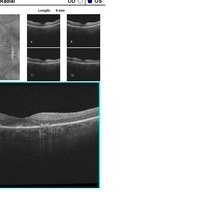

Plaquenil Toxicity OCT OD

Jun 8 2016 by John S. King, MD

HD OCT of patient with 6 year hx of plaquenil use. "flying saucer" sign

Condition/keywords: plaquenil toxicity

Plaquenil Toxicity OS OCT

HD OCT of pt with 6 year hx of plaquenil use. "flying saucer" sign